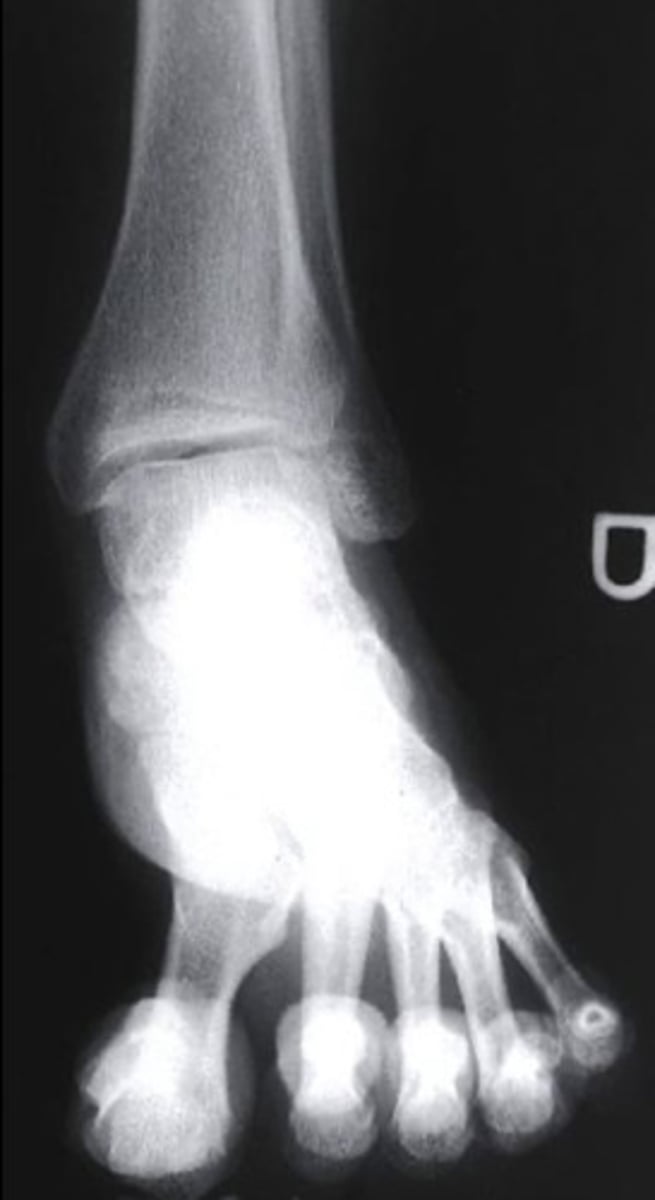

what radiograph view is this?

oblique

3 multiple choice options

what radiograph view is shown here?

lateral

what do the orange circles in these radiographs indicate about the patient's injury to the anterior process of the calcaneus?

avulsion fracture

2 multiple choice options

after revealing a non-displaced fracture of the anterior process of the calcaneus, which of the following options will allow for the structure to heal?

controlled ankle movement (CAM) walking boot

which structure of the foot is highlighted by the blue line?

talus

what is this view?

AP